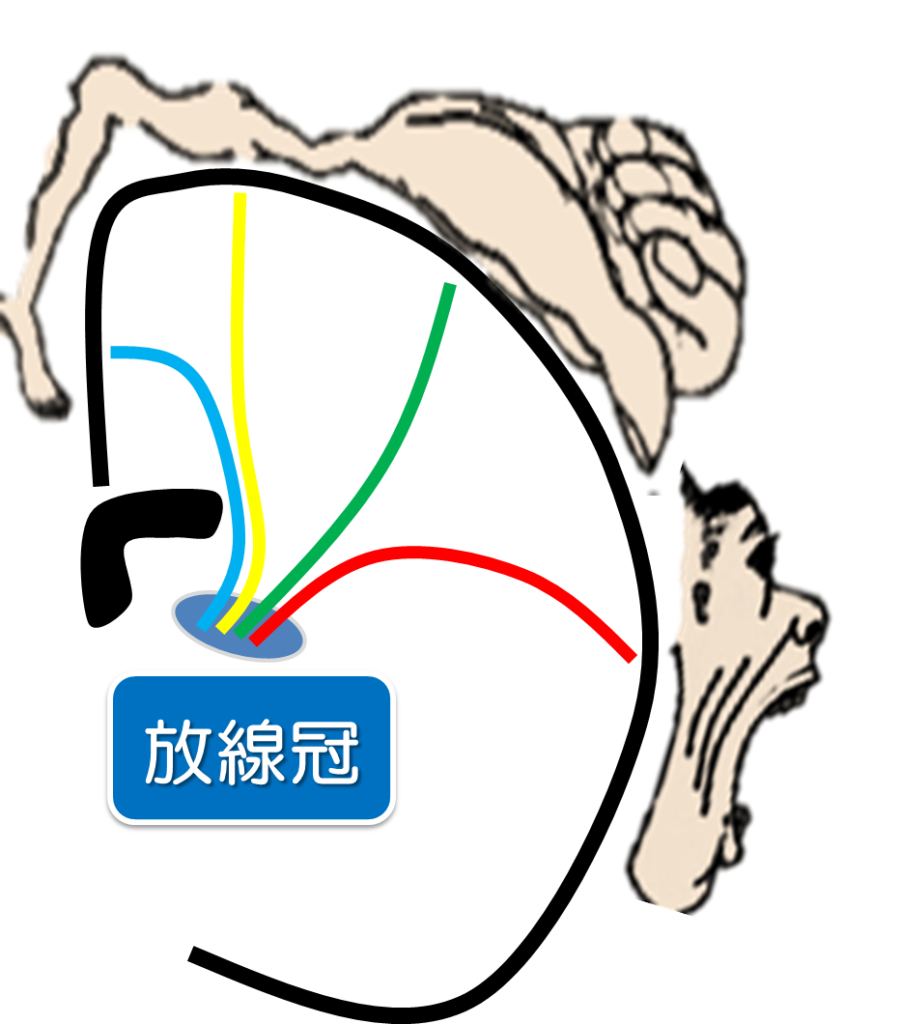

皮質脊髄路 錐体路 を脳画像から簡単に見つける方法 運動麻痺を理解する5つの見るべきポイントとは リハアイデア

錐体路とは イラストを用いて説明します リハビリの引き出し